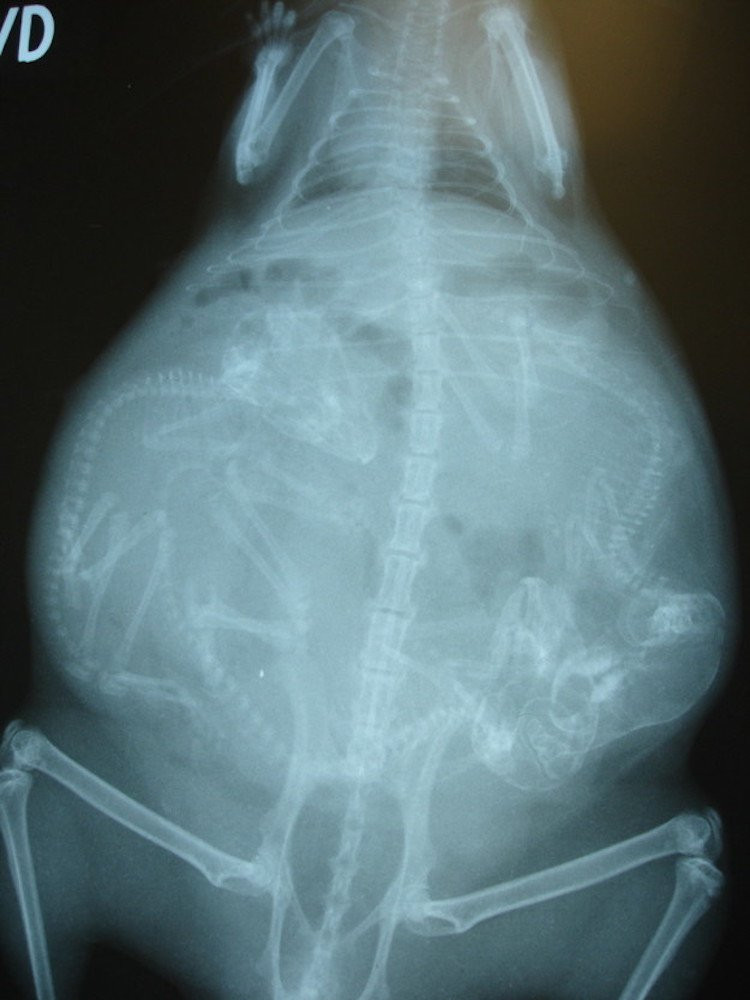

Le saviez-vous ? Les singes sont des mammifères de l'ordre des primates. Malgré d’évidentes ressemblances avec nous les bipèdes, les scientifiques ont mis de nombreux siècles à prouver le lien étroit qui existe entre les singes et l’homme.

Après une période de gestation variant de 6 à 9 mois selon certaines races, les femelles donnent naissance principalement à un petit à la fois. A peine sorti, le bébé s'accroche au pelage de sa mère, tête, dort et crie. (Toute ressemblance…)

Le baby-sitting est une affaire de famille. En plus du père, ce sont souvent les frères et sœurs qui s'occupent des petits.